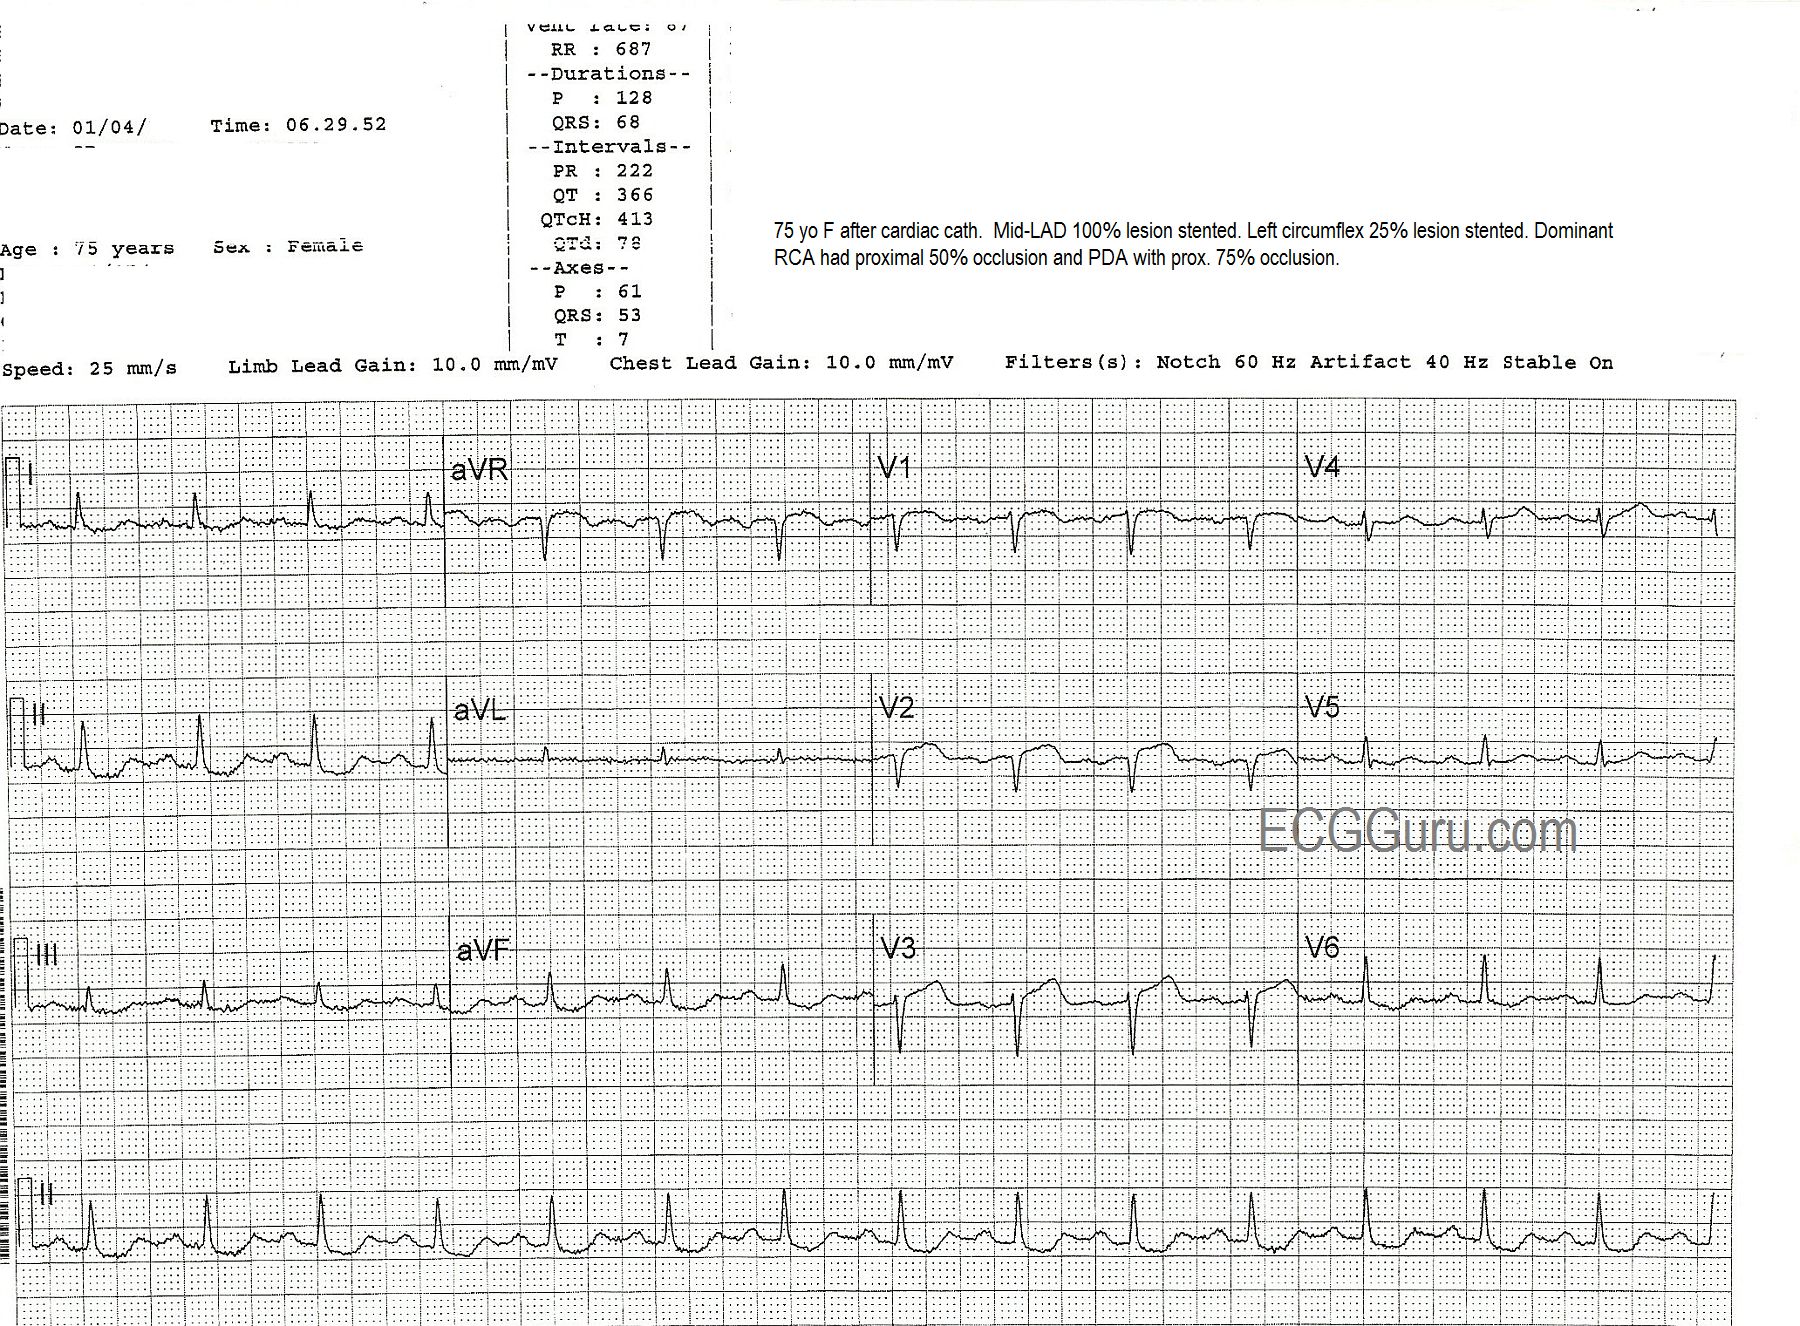

Anterior Wall M.I.

This series of three ECGs is from a 75-year-old woman who came to the Emergency Dept. with chest pain.  The first ECG shows ST elevation in V1, V2, and V3, with generally low voltage in the QRS complexes. There is some coving upward of the ST segment in aVR, which can suggest a very proximal lesion of the left coronary artery (LCA).  She was taken to the cath lab, where it was discovered that she had a 100% occlusion of the midportion of the anterior descending branch of the left coronary artery, which was repaired and stented.  The second ECG, taken after the angioplasty, shows some Q waves in V1 and V2, with poor R wave progression in the V leads.   A 25% occlusion of the obtuse marginal branch of the circumflex artery was stented two days later. The third ECG was obtained after that procedure.  It shows that the Q waves have disappeared in the anterior leads (possibly due to different technicians performing the ECGs with different lead placement).  It also shows marked T wave inversion in I and aVL, representing ischemia in the lateral wall, and in all the chest leads, representing ischemia in the anterior wall.  The QTc is prolonged in this third ECG at 479 ms.  It is not known what medications the patient was on.  This patient also had a 50% proximal occlusion in the RCA and a 75% occlusion in the posterior descending artery.   This is a good example of a patient with extensive coronary artery disease who finally presented for treatment when she developed ST elevation M.I.